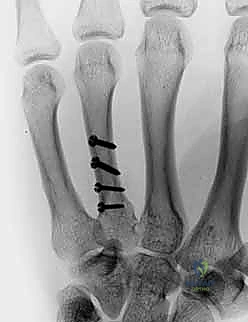

2. التثبيت الداخلي بالصفائح والبراغي المصغرة (Mini-Plates & Screws)

في حالات الكسور المتفتتة (Comminuted) أو الكسور الحلزونية الطويلة التي تميل للانزلاق، يلجأ الدكتور هطيف إلى التثبيت الداخلي المفتوح (ORIF). يتم استخدام صفائح معدنية دقيقة جداً (مصنوعة من التيتانيوم) تتناسب مع حجم عظام اليد.

* الميزة: تثبيت صلب وقوي جداً (Rigid Fixation)، مما يسمح للمريض ببدء العلاج الطبيعي وتحريك أصابعه في اليوم التالي للعملية، وهو أمر بالغ الأهمية لمنع تيبس الأوتار.

معرض الصور الشعاعية: تقييم النتائج الجراحية (Post-Op X-rays)

النجاح الحقيقي يُقاس بالاستعادة المثالية للشكل التشريحي للعظم. توضح هذه الصور الشعاعية بعد الجراحة الدقة المتناهية في إعادة محاذاة العظام وتثبيتها.

التثبيت المحكم يسمح بالشفاء العظمي الأولي (Primary Bone Healing) دون تكوين كتلة عظمية كبيرة (Callus) قد تعيق حركة الأوتار المنزلقة فوقها.

تعرض شاب رياضي لكسر متبدل ومعقد في العظمة المشطية الثانية والثالثة إثر سقوط عنيف أثناء تدريب رياضي. كان التخوف الأكبر هو فقدان قوة القبضة التي يعتمد عليها في مسيرته. أجرى أ.د. محمد هطيف جراحة تثبيت داخلي باستخدام صفائح التيتانيوم المصغرة. بفضل التثبيت القوي، بدأ المريض العلاج الطبيعي في اليوم الثالث، وعاد لممارسة نشاطه الرياضي الكامل بعد 8 أسابيع فقط.